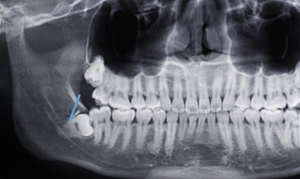

答:本x線片示48近中低位埋伏阻生,且牙根緊鄰下牙槽神經(jīng)管,拔除時(shí)需注意充分去除近中方向的牙體冠方阻力及遠(yuǎn)中的牙槽骨阻力,挺出牙根時(shí)盡量做到一次完成,減少牙根與神經(jīng)管的摩擦,降低神經(jīng)受損風(fēng)險(xiǎn)。

遠(yuǎn)中:骨阻力 近中:牙體冠方組織

第一:確定阻力去骨的范圍: